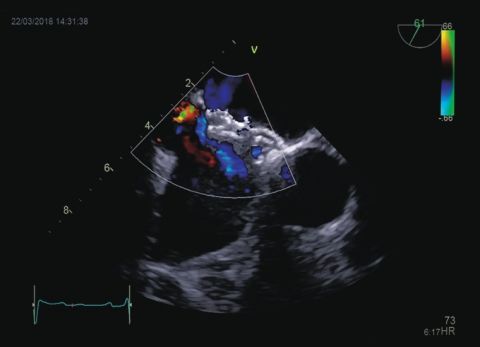

Wideo Echokardiografia. Przypadek 6

prof. dr hab. n. med. Piotr LipiecPacjentka z pogorszeniem tolerancji wysiłku, długotrwałą gorączką i szmerem skurczowo-rozkurczowymi; w wywiadzie narkomania.